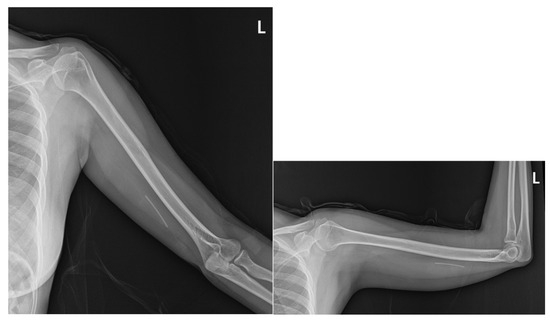

2.1. Prior Imaging Included Radiography (Figure 3), Which Confirmed the Implant’s Location, and Ultrasound (Figure 4), Which Demonstrated Its Proximity to the Ulnar Nerve